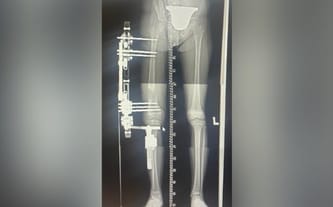

Cel zbiórki: Operacja przygotowawcza do wydłużenia nóżki w Paley Institute

Niedorozwój i skrócenie kości udowej w prawej nodze